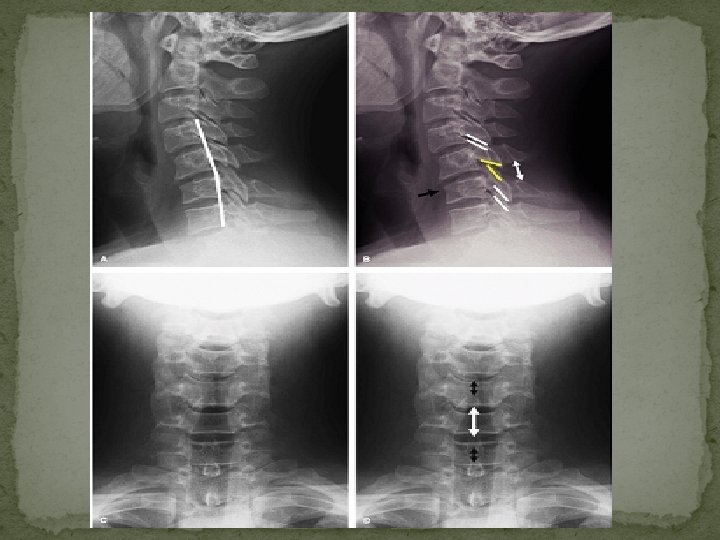

� Anterior translation of C 1 evidenced by the abnormally wide (>> 5 mm) anterior atlantodental interval (AADI) � Anterior position of its spinolaminar line (yellow line in B) with respect to that of C 2 -3 spinolaminar lines

Plain film findings: Lateral view: The findings of AS seen in neutral position become exaggerated upon flexion and are reduced in extension � Widening of the interspinous distance at one level (“fanning”), relative to adjacent levels � Incongruity and lack of parallelism of the contiguous facets � Disc space is widened posteriorly and narrowed anteriorly � Small anterior superior compression fractures of the subjacent vertebral body � Increased thickness of the prevertebral soft tissues as a result of hematoma formation

UNSTABLE: �▪Anterior translation of the vertebral body >3. 5 mm relative to the subjacent vertebra �Vertebral body angulation >20 degrees relative to the adjacent vertebra.